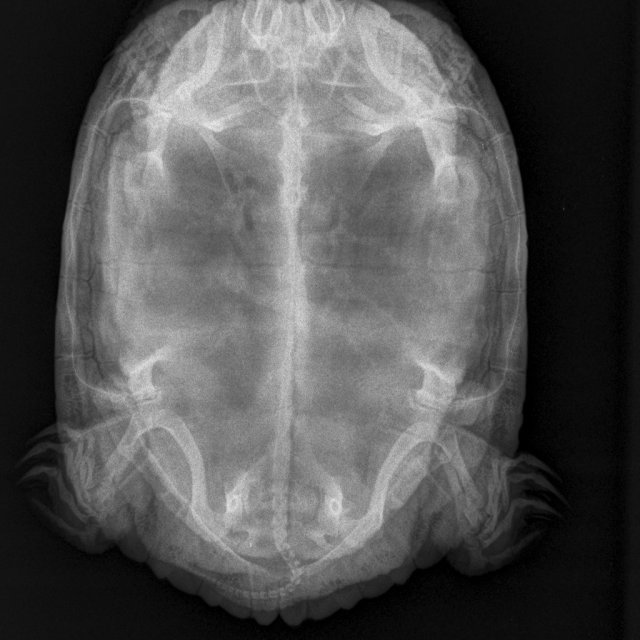

Я из Москвы, мне 49 лет. Черепаха красноухая, 10 лет, вес 1 кг 700 гр. живёт в аквариуме большом, есть лампа УФ и накаливания (включены целый день, меняем раз в полгода), есть фильтр внешний, нагреватель, мостик, грунта нет. Очень вялая - целый день отдыхает или спит, есть особо не хочет - рептомин не ест, грудку или печень раз в 5 дней после уговоров может съесть порцию небольшую, меньше чем её голова. Заметили болезнь уже недели три назад, две недели делали уколы. Последний укол 16 апреля. Прокололи курс лекарств по совету герпетолога - Кальций борглюконат через день,  Витам (1 раз в 3 суток), дексаметазон, фуросемид. По старому рентгену герпетолог сказал, что возможно яйца жировые, по свежему рентгену он никаких яиц не видит. Сейчас ничего больше не назначили нам. Я очень за черепаху волнуюсь

Мягкие ткани Мелкий _ 10 kg-Брюшная полость VD-19.04.2025-19_58_38-378.JPEG

Мелкие животные_Рептилии-Брюшная полость VD-19.04.2025-19_58_41-685.JPEG

Рентген 2 нед назад (2).JPEG

Рентген 2 нед назад.JPEG

Рентген 2 недели назад.JPEG

по симптомам нужно исключать/подтверждать анемию и проблемы с печенью. К сожалению дистанционно тут ничем не помочь. Вы сделали ей курс уколов кальция - если бы там была рядовая проблема авитаминоза/формирования яиц, то это бы помогло.